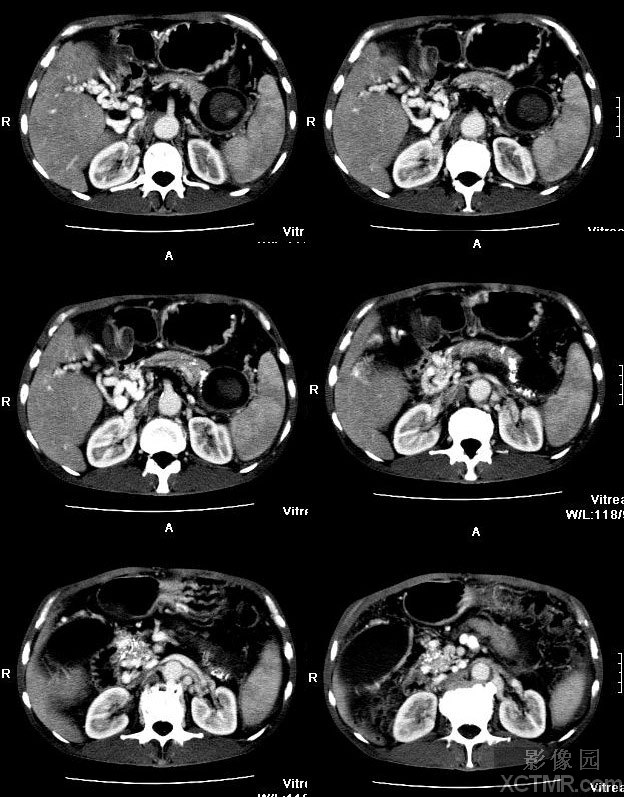

术前门静脉系统ct图

图示:增强ct术后6天复查,肝内外门静脉完全恢复正常血流充盈

增强ct门静脉期可见门静脉血流通畅

腹部ct提示肝门部门静脉结构紊乱,大量侧支血管,巨脾